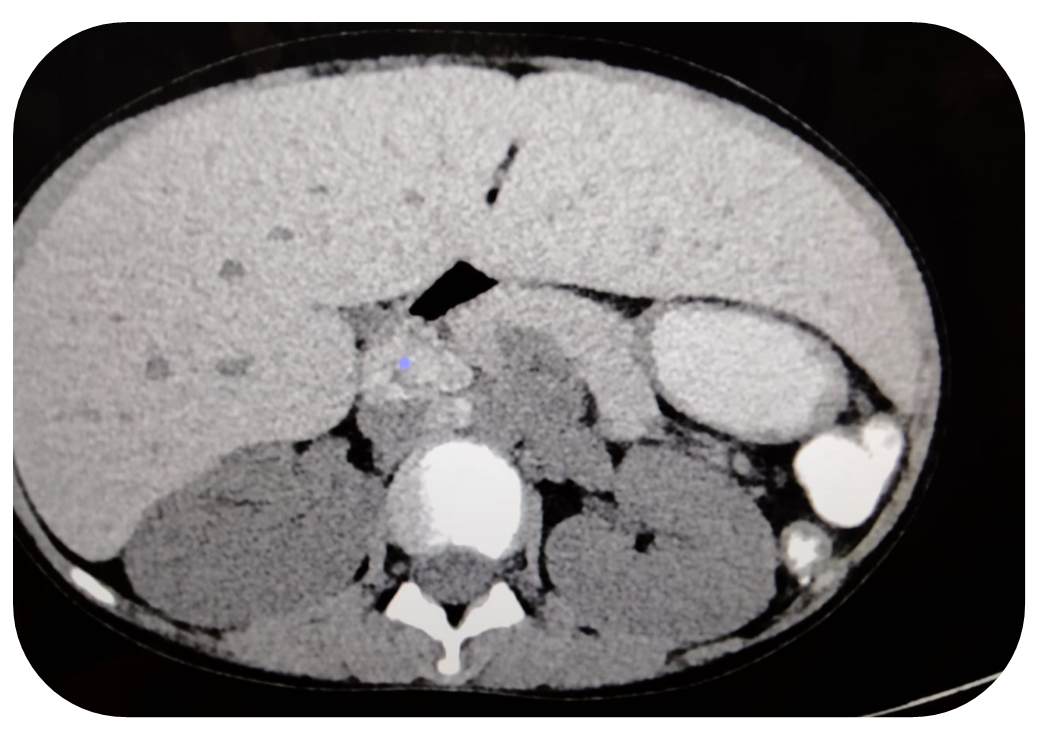

In this case, a 13-year-old girl known case of thalassemia major, presented to ER department with complain of generalized body weakness and paleness of skin for one month. She receives blood transfusions twice a week and had a splenectomy in the past; her family history was unremarkable. Patient was referred to radiology department for CT abdomen triphasic protocol, which showed findings of Hemochromatosis. After the diagnosis was made, iron chelation therapy was started to reduce the burden of iron built up from repeated transfusions. Chelating agents like deferoxamine, deferiprone, or deferasirox are commonly used, depending on factors such as iron levels, side effects, and patient preference. Treatment is guided by serial monitoring of serum ferritin and MRI-based liver iron concentration (LIC), which allow clinicians to adjust chelation intensity over time.

Figure 1. Shows enlarged hypodense liver with iron deposition.

Figure 2. Shows multiple enlarged hypodense areas at porta hepatis representing iron deposition nodes.

Figure 3. Shows iron deposition in liver and nodes representing hemochromatosis secondary to thalassemia.